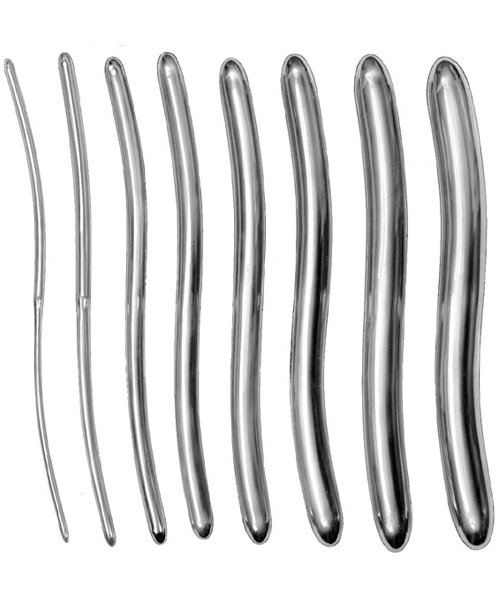

- Surgical Instruments, Urology

Gall Duct Dilator

- Size : 21 CM - 8 1/4"

- Read more

-

- Surgical Instruments, Urology

Gall Duct Dilator

- Size : 21 CM - 8 1/4"

- Read more

-

- Surgical Instruments, Urology

Gall Duct Dilator

- Size : 32 CM - 12 1/2"

- Read more

-

- Surgical Instruments, Urology

Gall Duct Dilator

- Size : 32 CM - 12 1/2"

- Read more

-

- Surgical Instruments, Urology

Gall Duct Dilator

- Size : 32 CM - 12 1/2"

- Read more

-

- Surgical Instruments, Urology

Gall Duct Dilator

- Size : 32 CM - 12 1/2"

- Read more

-

- Surgical Instruments, Urology

Gall Duct Dilator

- Size : 32 CM - 12 1/2"

- Read more

-

- Surgical Instruments, Urology

Gall Duct Dilator

- Size : 32 CM - 12 1/2"

- Read more

-

- Surgical Instruments, Urology

Gall Duct Dilator

- Size : 32 CM - 12 1/2"

- Read more

-

- Surgical Instruments, Urology

Gall Duct Dilator

- Size : 32 CM - 12 1/2"

- Read more

-

- Surgical Instruments, Urology

Gall Duct Dilator

- Size : 32 CM - 12 1/2"

- Read more

-

- Surgical Instruments, Urology

Gall Duct Dilator

- Size : 32 CM - 12 1/2"

- Read more

-

- Surgical Instruments, Urology

Gall Duct Dilator

- Size : 32 CM - 12 1/2"

- Read more